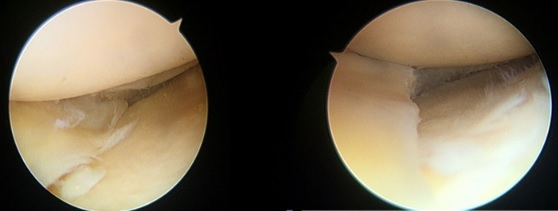

파열의 크기가 아주 크지 않아서 일부분의 반월연골판을 제거하는 부분 절제술을 시행한 경우에는 대부분 양호한 경과를 보인다.

이에 반해 반월연골판을 거의 모두 떼어내야만 하는 아전 절제술이나 전부를 제거하는 전 절제술을 시행하게 되는 경우에는 다양한 임상 경과를 보인다.

어떤 환자들은 추가적인 치료 없이 경과를 관찰하는 정도로 그치지만, 오히려 일부 환자들은 절제술을 시행한 후에 퇴행성 관절염이 빠르게 진행하고 통증이나 부종이 계속돼 일상생활이 힘들 정도인 경우가 있는데 이 때는 동종 반월연골판 이식술을 고려할 수 있다